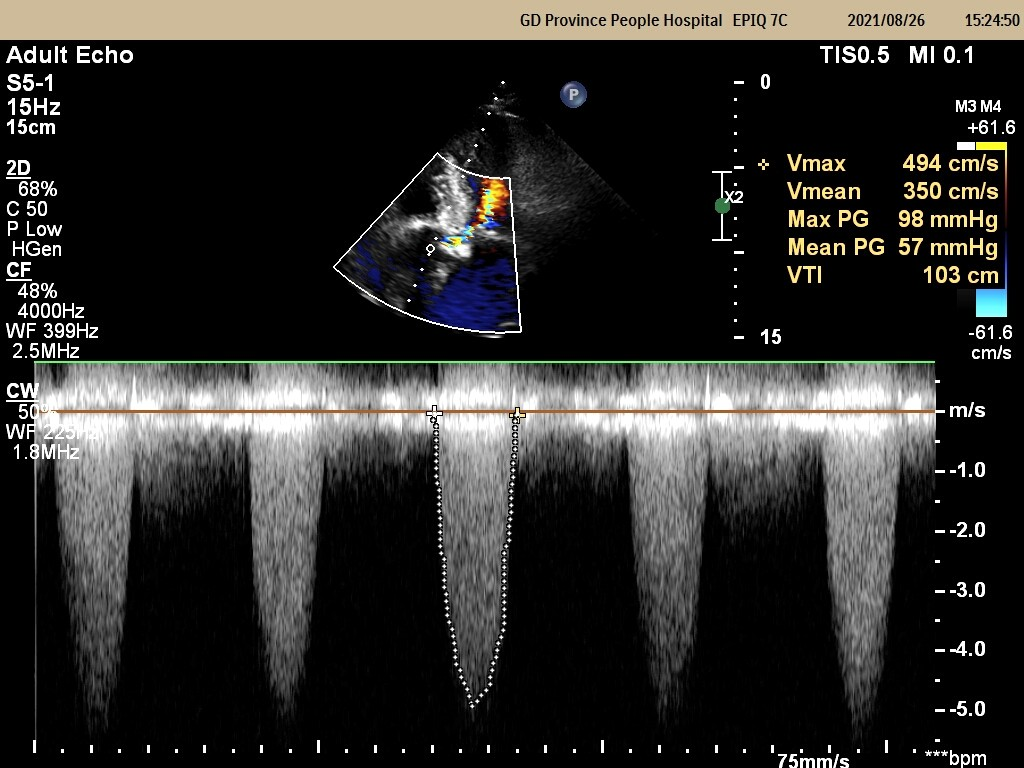

重主动脉瓣口流速 4.9m/s;峰压差 98mmHg;平均压差57mmHg;LVEF 55%

重度主动脉瓣狭窄并中度反流 轻度二尖瓣反流 轻度三尖瓣反流